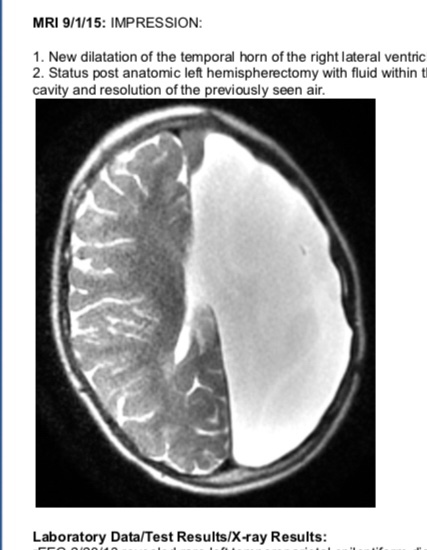

Thank you for all the prayers. The surgeon came out about half and hour ago to let us know they are done. She did great. He removed more of the frontal lobe to make sure everything is disconnected. He did see a “suspicious area” that looked like scar tissue but is where the scans were showing some fibers were still connected. He just removed that whole area to be sure. She has now had more of an anatomical hemispherectomy but not completely. He didn’t want to disrupt any other areas unnecessarily. They finished earlier than we thought and he didn’t even need to put a drain in. We are relieved to be done with this leg of the journey. On to rest and healing.